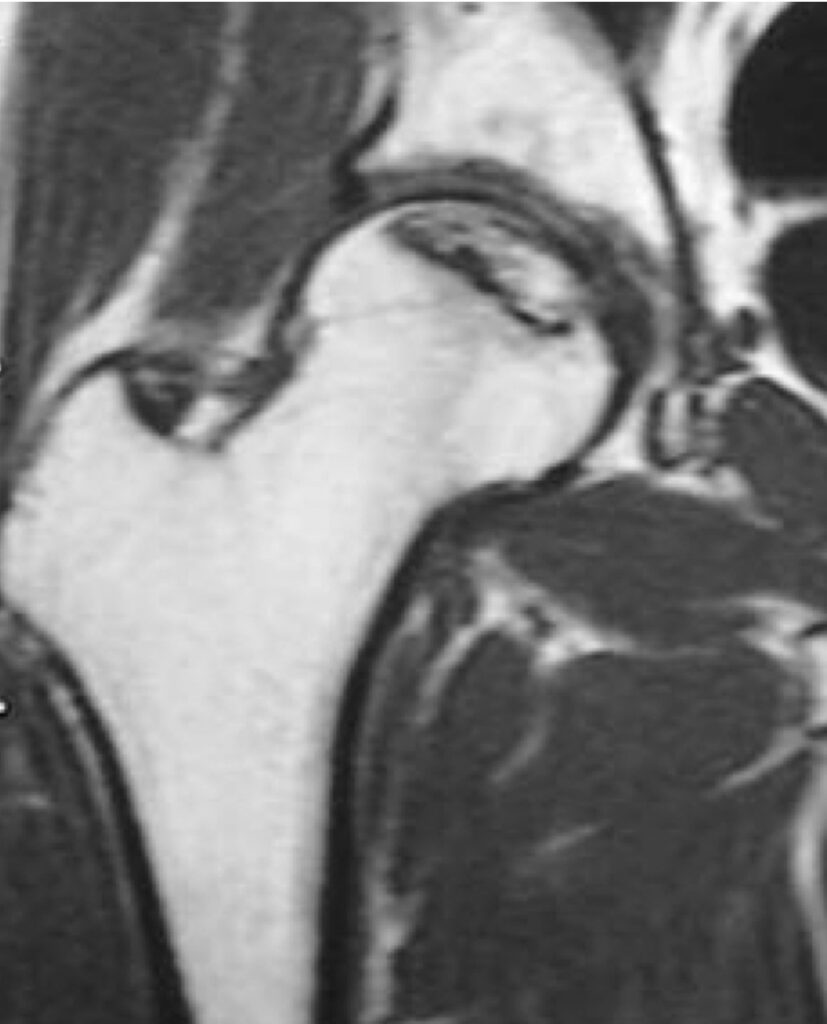

股関節の中心である大腿骨頭が壊死してつぶれるために痛みを生じる病気です。アルコールの多飲やステロイドの使用に関連しているとも言われていますが、いまだにはっきりしておらず国の難病に指定されています。骨頭の破壊が強ければ人工股関節置換術が必要になることがあります。

大腿骨頭壊死のMRI